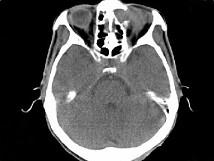

问题 男,53岁,近两年来渐进性头痛,伴左眼球外突,并向前下方移位,CT检查如图,最可能诊断为 ( )

选项 A、眶内炎性假瘤 B、眼格氏病 C、左额窦癌 D、左额窦黏液囊肿 E、额窦炎症

答案 D